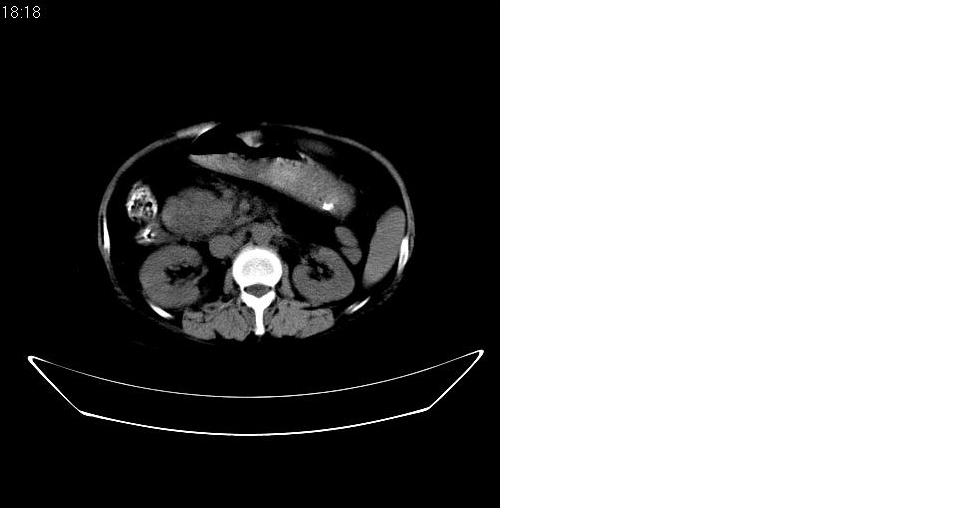

以下是引用守望可可西里在2007-1-20 23:09:00的发言:[br][br] 胰头癌,胆总管梗阻、截断,肝内外胆管重度扩张,肝内边缘部分的圆形低密度病灶多能与扩张的胆管较为连续,暂不考虑转移。病人没有黄疸吗?

以下是引用天南地北在2007-1-20 23:22:00的发言:[br]1:按照肿块的位置及胆总管的形态:考虑胆总管(中下段)癌并肝内胆管扩张,累及胰头。2:不排除胰头癌并肝内胆管扩张。[br]肝内病灶看起来还是扩张的胆管,不考虑转移先。